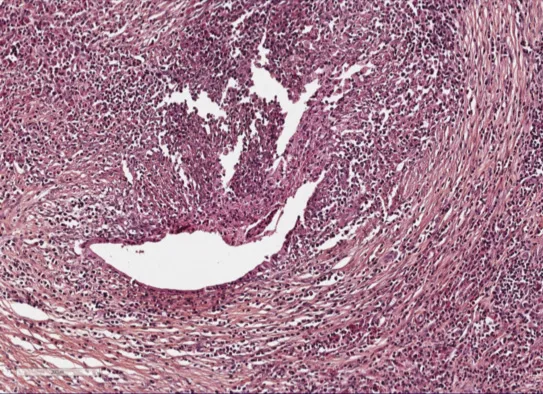

2. Infiltration lympho-plasmocytaire marquée sans infiltration à poly­nucléaires neutrophiles (Fig. 1).

3. Fibrose « storiform » (arciforme).

4. Phlébite oblitérante.

5. Abondance de plasmocytes à IgG4 (> 10 plasmocytes à IgG4 par grand champ). Cette lésion dénommée LPSP pour Lympho-Plasmocytic Sclerosing Pancreatitis est la signature de la PAI de type I (Fig. 2).

Figure 1. LPSP sur une pancréatectomie. Infiltration lymphoplasmocytaire péri-canalaire, fibrose storiform et phlébite oblitérante